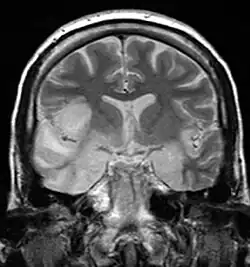

MRI scan image shows high signal in the temporal lobes and right inferior frontal gyrus in someone with herpes simplex encephalitis.